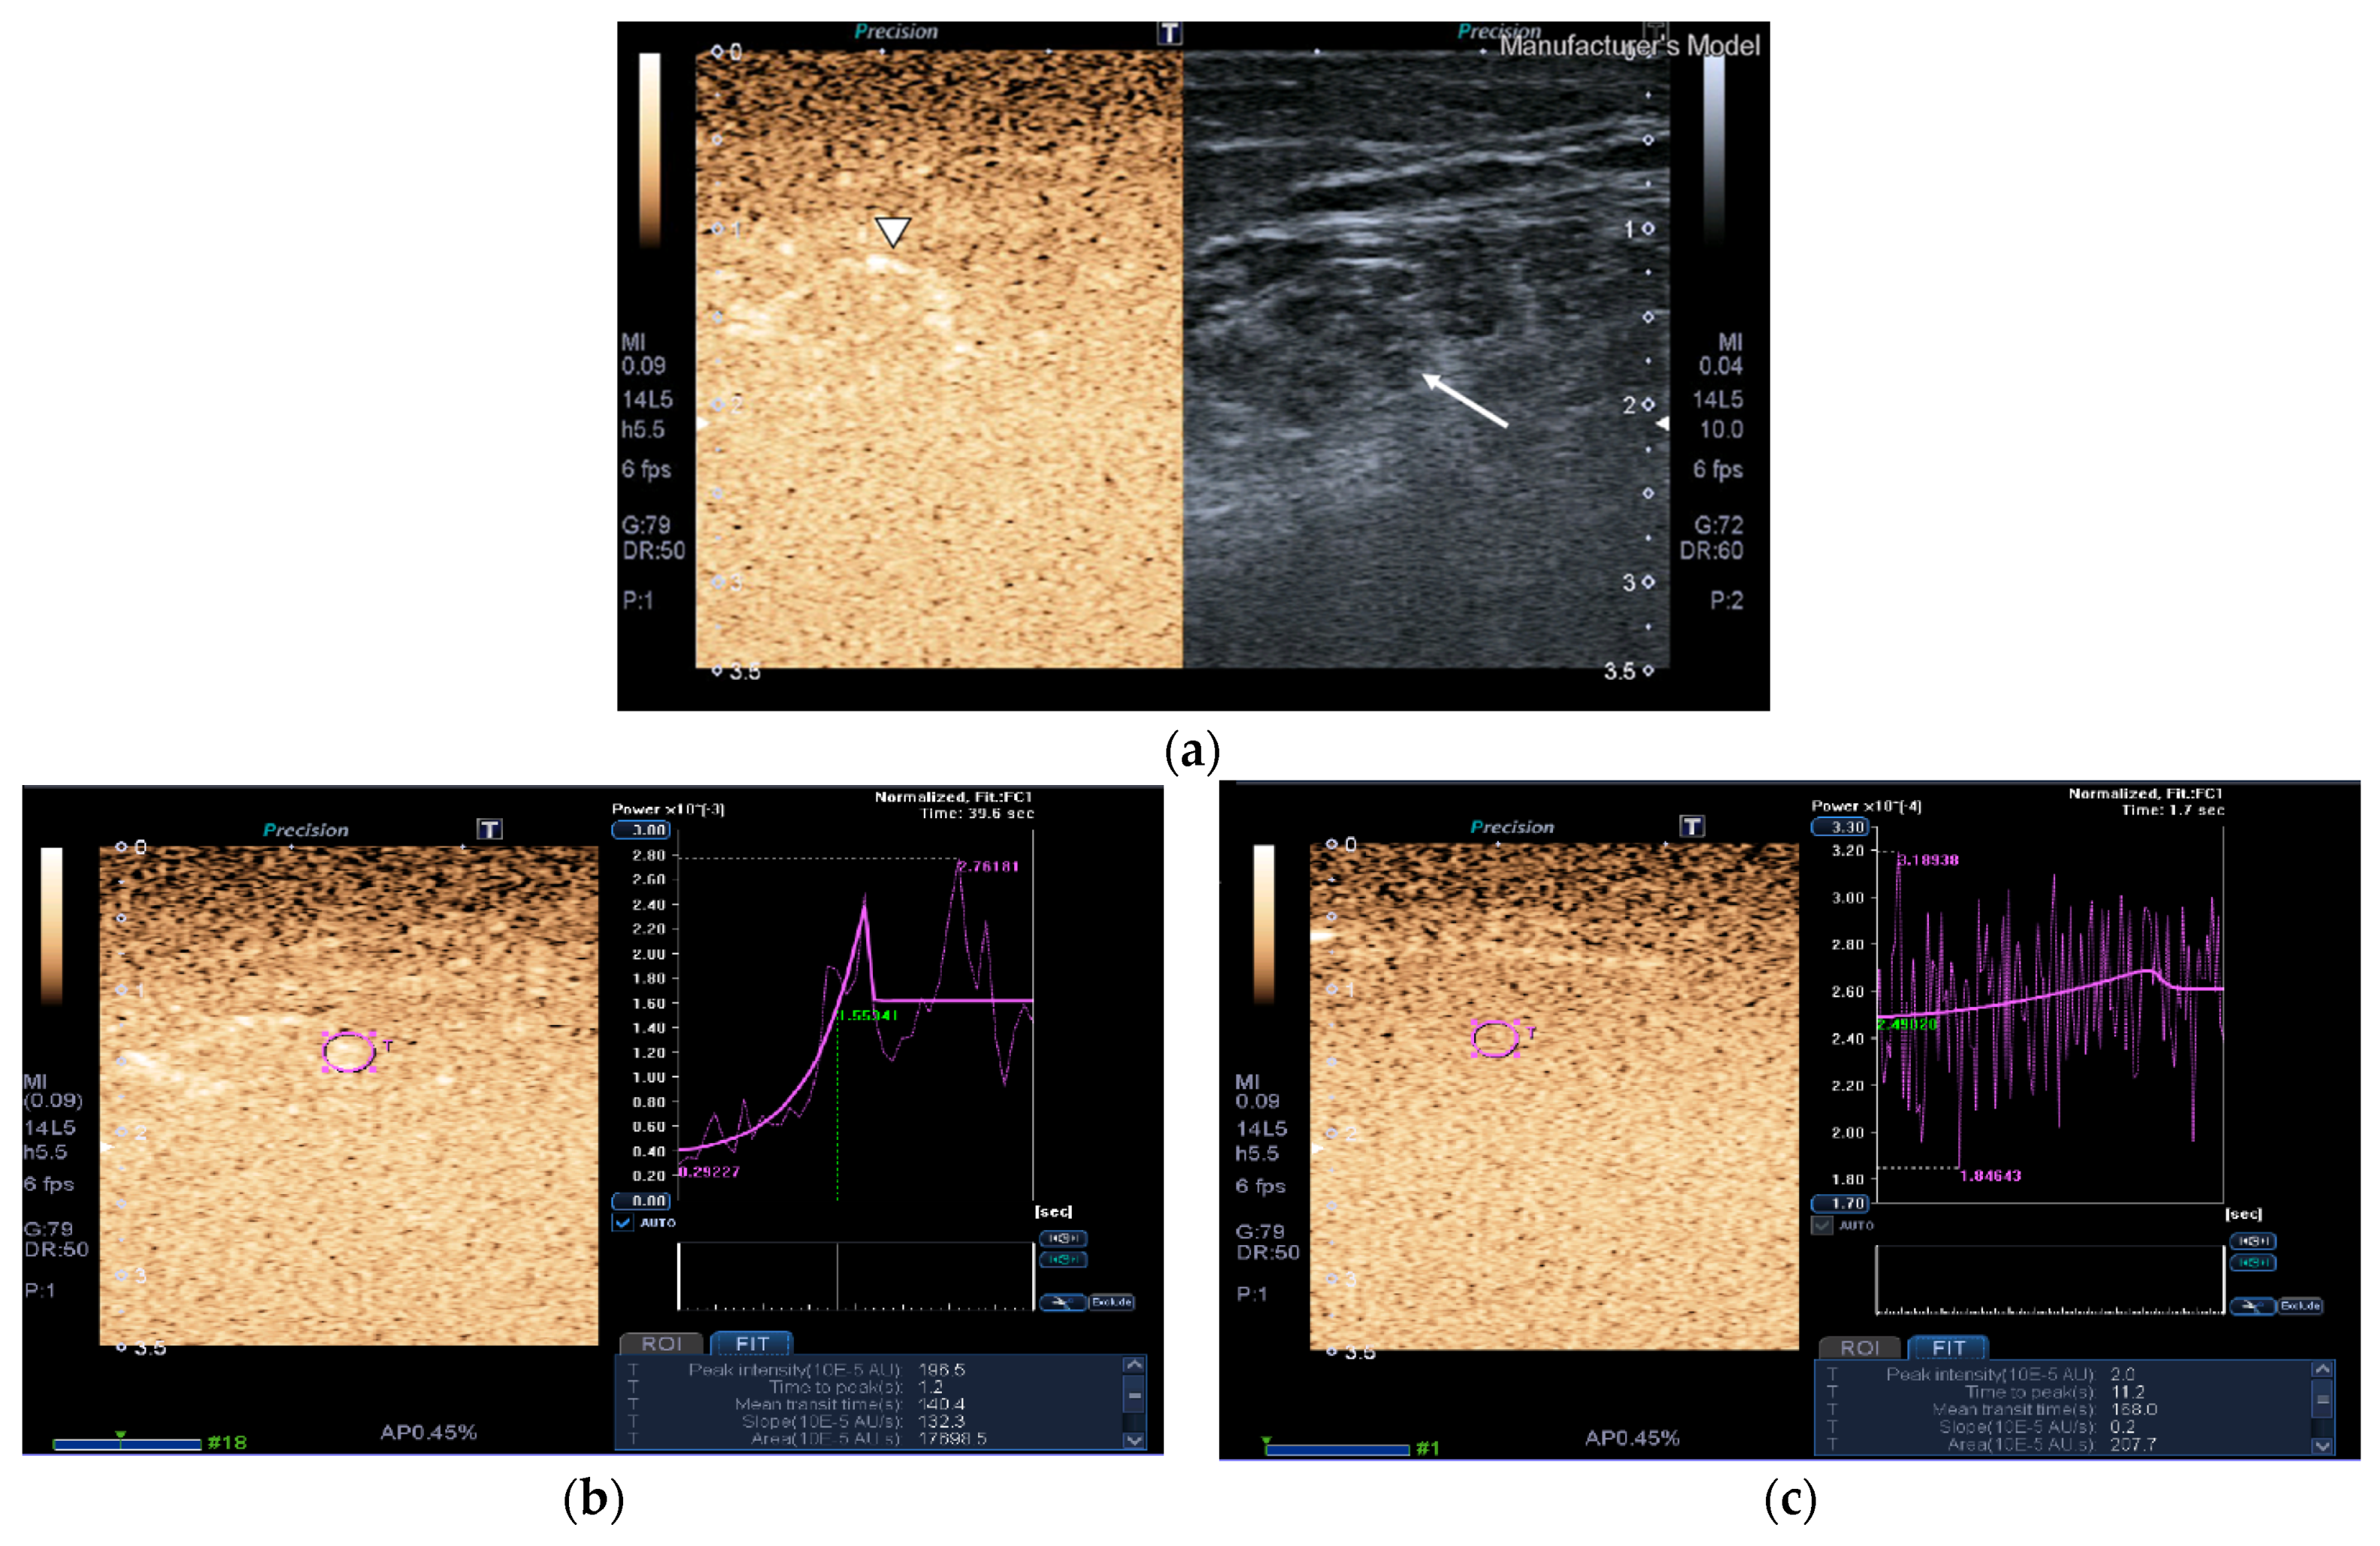

Figure 3.

Transversal QRF muscle of a matched healthy control (85 years old). (a) Transversal ultrasonography scan shows the QRF muscle (arrow) and vascularization after contrast-enhanced ultrasound (CEUS) administration (arrowhead). CEUS image and time–intensity curve analysis are shown using the built-in software. (b) ROI (pink circle) in the area of strongest enhancement indicates maximum perfusion in the QRF. (c) ROI (pink circle) in the area of lowest enhancement indicates minimum perfusion in the QRF.

Images of the peak maximum and minimum CEUS intensity of a patient and a healthy control are shown in Figure 3 and Figure 4.